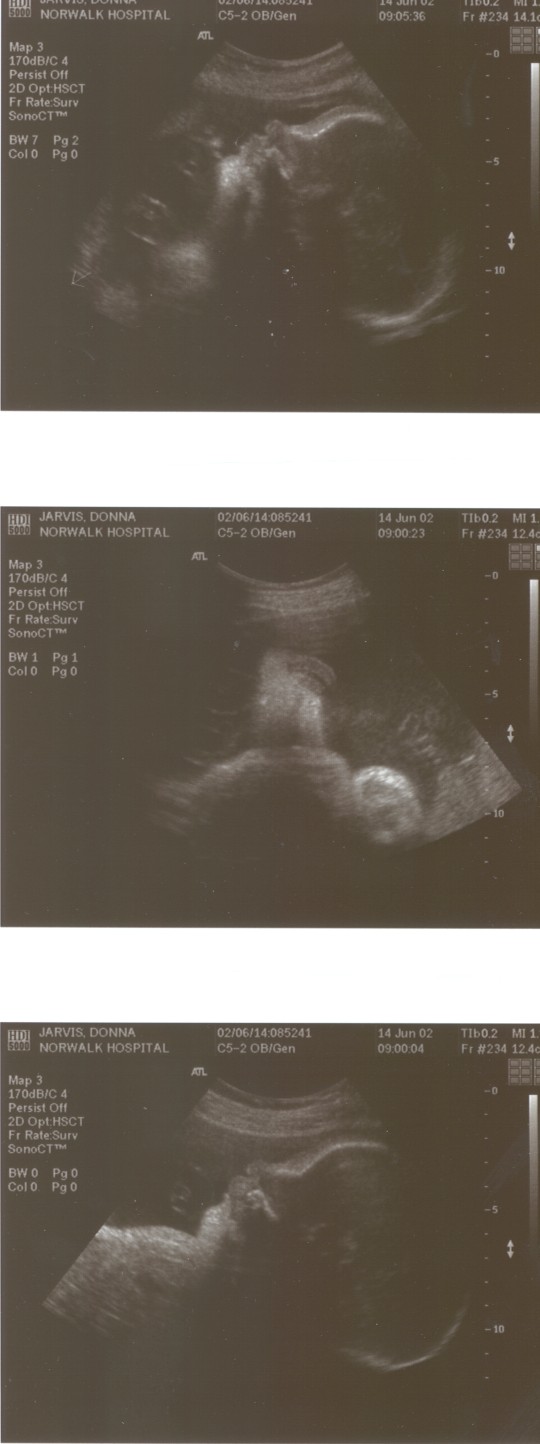

6/15/02 (Week 32)- We had our last ultrasound this week. The baby appears in good health and is estimated at 3 pounds, 14 ounces which is around the median size. We saw her lips and her tongue and watched her yawn. We also saw her little heart beating and watched her kick. Mom, however, is getting more and more uncomfortable - back aches, feet hurt, hands, feet and legs swollen. And she gained a little too much weight this visit, so we are now watching what we eat. We picked out our baby announcements this week and the room will finally be painted next week, so we are making some progress on getting everything done before the baby arrives!